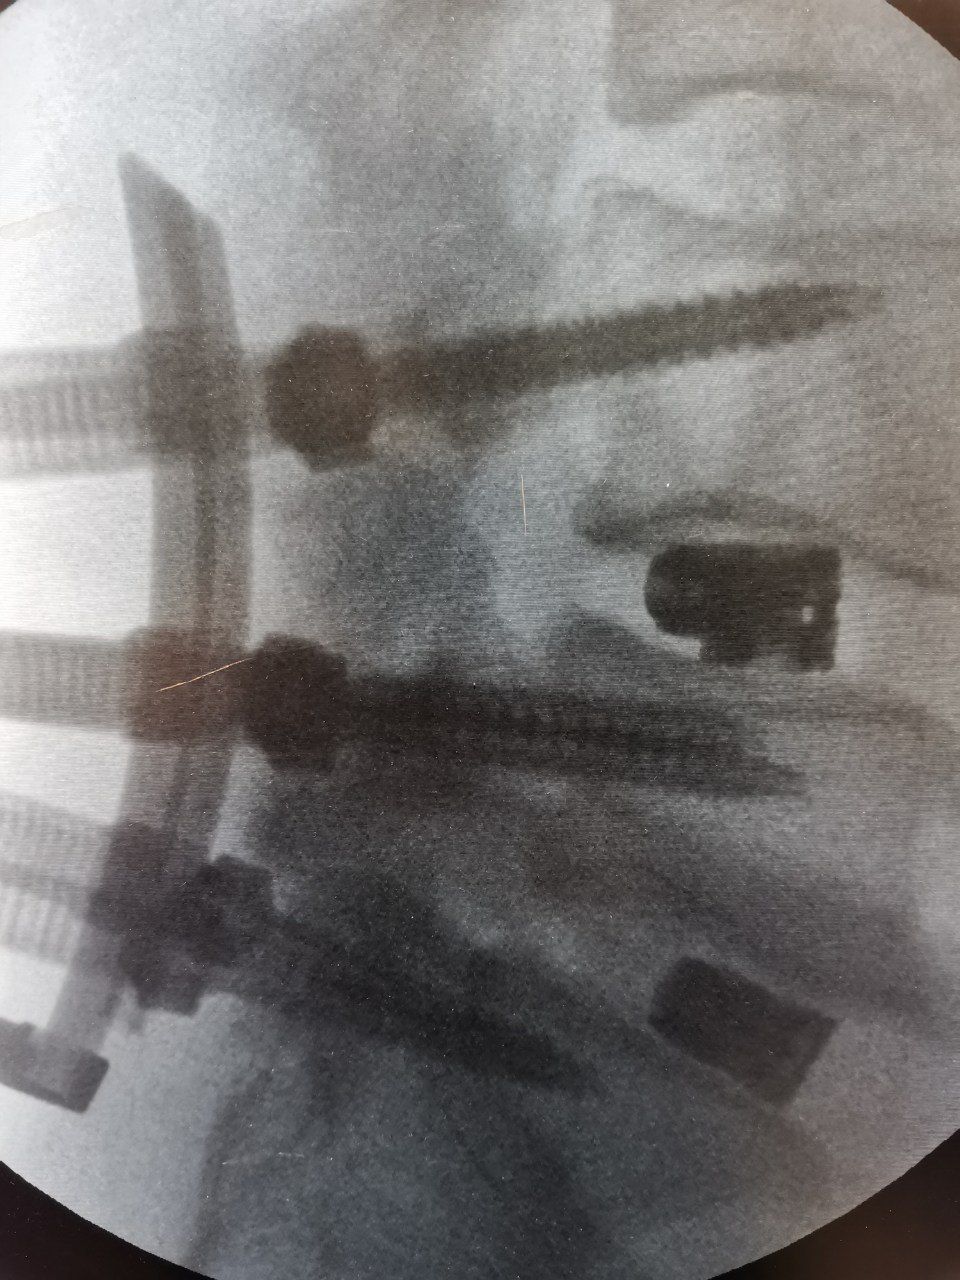

Foto e video